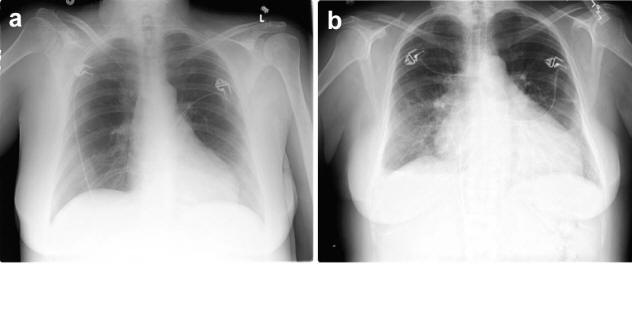

Severe Congestive Heart Failure

Severe Congestive Heart Failure Images